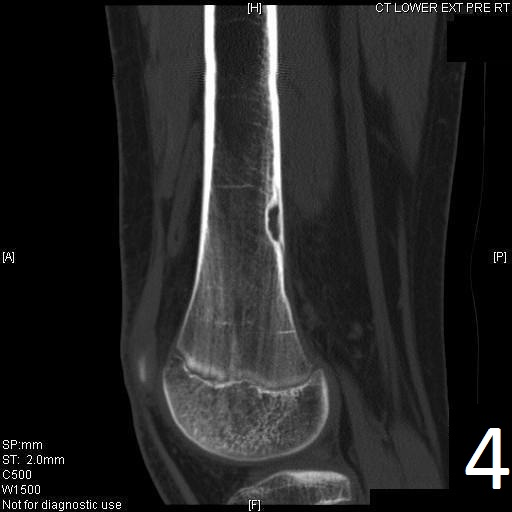

CT

• Useful for determining the true extent of the lesion

• Demonstrates well defined sclerotic borders

• Demonstrates expansile nature and scalloping of bone

• Useful for demonstrating internal trabeculations

Fig. 4

Fig. 4-5: Sagittal (Fig. 4) and axial (Fig. 5) CT reconstruction of the lower extremity shows a well circumscribed, small sclerotic cortical lesion consistent with a fibrous cortical defect.